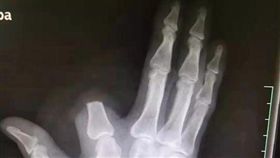

百步蛇毒吻!他慘叫手腫成「黑麵龜」

又有登山客遭到百步蛇咬傷!屏東笠頂山近日一直都有百步...

2019/11/26 17:04

消防員遭百步蛇咬 5分萎縮如黑棗?

夏天到了,又是蟲蛇活躍的季節,近日網路上流傳一張消防...

2018/08/16 17:59